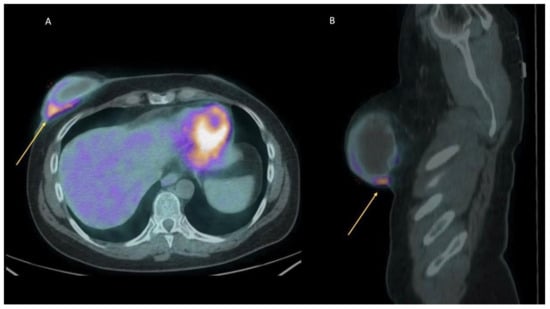

| [18F]FDG PET/CT | -No uptake or only faint uptake around the breast implant. -No axillary lymph node uptake, or just faint uptake in normally-sized nodes, vascular hilum well-visible. | -Focal uptake around the implant and in axillary, mediastinal (usually internal mammary), and supraclavicular enlarged lymph nodes; -Pericapsular fluid collection may be present, with detectable faint activity; -Fluid effusion between the breast implant and the host fibrous capsule causing asymmetry and swelling of the breast can be a sign of breast implant-associated anaplastic large-cell lymphoma. | Even bearing in mind the clinical history of each patient, both visual and semiquantitative analysis (SUVmax) do not discriminate among inflammation, infection, and neoplastic foci, because they take up glucose similarly. The clinical setting of each focal uptake (implantation for oncological versus aesthetic reasons) and any morphological findings (see above) may lead the clinician to follow-up or to collect a biopsy specimen, and eventually fluid culturing, to rule out granuloma/infection versus node metastases or lymphoma or SCC associated with breast implants. |